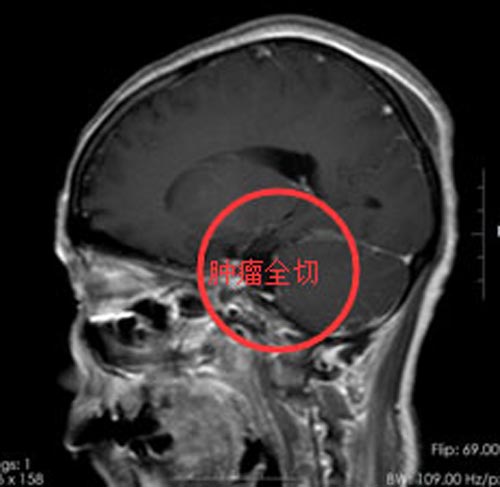

入住综合神经外科后,医生给陈阿姨做了更详细的检查,结果诊断为:1.左侧小脑幕下占位,考虑脑膜瘤;2.继发性左侧三叉神经痛。和陈阿姨及家属详细地介绍了手术方案,由鲁明副院长主刀,在全麻下行“左侧小脑幕下脑膜瘤切除术”。术中见颅窝靠近右侧岩斜区黄白色肿物,质硬,血供一般,筋膜粘连紧密,边界较清,用吸引器分块切除黄白色肿瘤,肿瘤组织根部位于右侧岩斜区内侧面,对桥脑有压迫,显微镜下将肿瘤全切,神经、血管保护良好,手术过程非常顺利。

术后,陈阿姨恢复良好,术前症状消失,已满意出院。

▲手术后